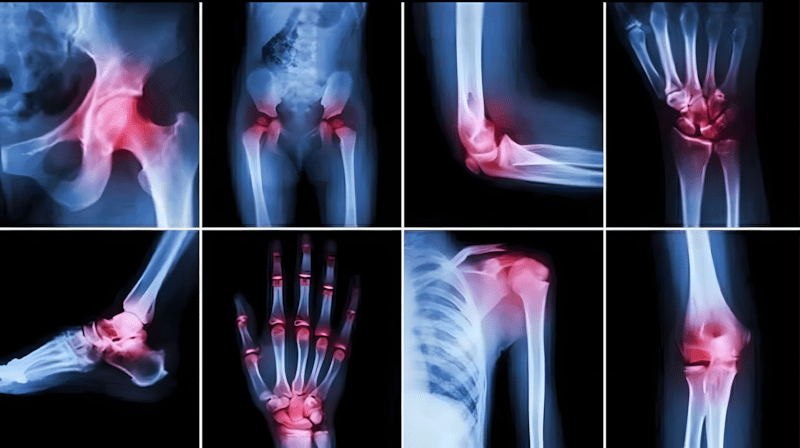

Gewrichtspijn is een van de meest voorkomende gezondheidsproblemen die mensen van alle leeftijden treffen, vooral bij het ouder worden, lange werkdagen of langdurig stilzitten. Gewrichten zijn de punten waar botten samenkomen en het lichaam flexibiliteit en beweging geven. Elke disfunctie of slijtage in deze gewrichten leidt tot aanhoudende pijn en stijfheid, en soms tot problemen met lopen of het uitvoeren van dagelijkse taken.

Maar de grootste uitdaging is dat de meeste mensen pas naar een oplossing gaan zoeken nadat de pijn ernstig is geworden, terwijl gewrichtsreconstructie een geleidelijk proces is dat vroegtijdige bewustwording en consistentie vereist. Is het echt mogelijk om gedegenereerde gewrichten te reconstrueren? Wat zijn de meest effectieve manieren om pijn te verminderen en de mobiliteit op een natuurlijke en veilige manier te verbeteren?